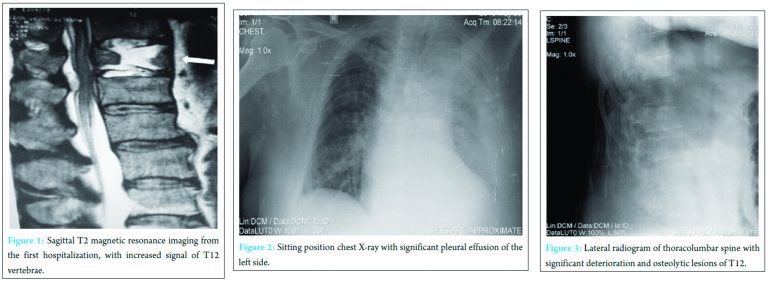

A 57-year-old obese (body mass index = 39) afebrile male patient, with breathing, constrained disturbances, resident of the province with domestic animals was transferred to our clinic from another hospital, where he was treated with bed rest for 2 weeks for spine fracture (Fig. 1) due to misdiagnosis. On admission, he claimed dyspnea, severe back pain of 2-month duration, left knee pain and swelling. He mentioned recent (2 months before) asymptomatic consumption of domestic poultry.

Physical examination revealed no pathologic neurological findings. His left osteoarthritic knee was swollen, while chest roentgenogram showed pleural effusion on the left side (Fig. 2). Lateral plain roentgenogram (Fig. 3) and computed tomography (CT)-scan (Fig. 4) of the spine revealed destruction of the T12-vertebral body and intervertebral discs T11-T12 and T12-L1 associated with paravertebral abscess formation (Fig. 5). White blood cells (WBC’s) were 17.5 k/Μl (normal limits: 4-10.0 k/Μl), C-reactive protein (CRP) was 23.1 mg/dL (<0.3 mg/dL), and ESR was 86 mm/1st h (0-20 mm/1st h).